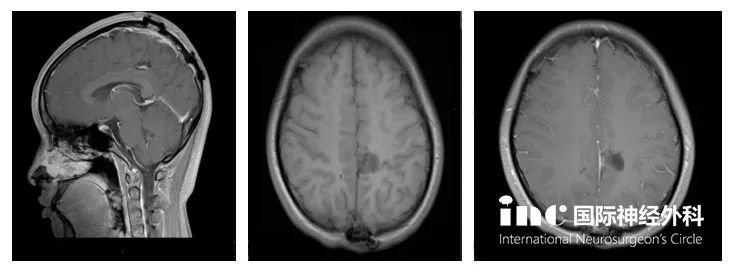

术前术后影像对比

(红色为术前,蓝色为术后)

核磁影像显示肿瘤全切并没有复发,无其他神经功能新症状。以下为术后3个月的MRI影像